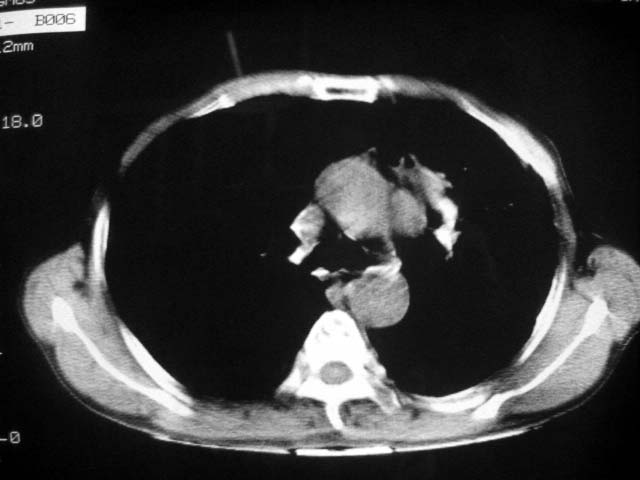

以下是引用zjzjr在2007-9-4 17:00:00的发言:[br]双上肺继发型结核伴左上肺空洞形成.慢性支气管炎伴肺气肿.